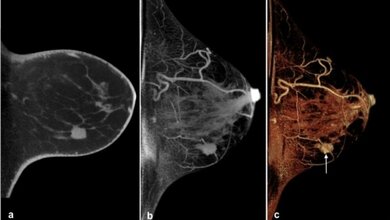

Kupferhaltiges T-förmiges Intrauterinpessar

Kupferhaltiges T-förmiges Intrauterinpessar mit Rückholfäden Wkimedia/CC BY-SA 2.0 fr

Hinsichtlich des Rückfallrisikos unbedenklich sind hormonfreie Intrauterinpessare („Kupfer-Spirale“, „Kupfer-Kette“). Darüber hinaus können Barriere-Methoden wie Kondome oder Diaphragma eingesetzt werden – allerdings mit Abstrichen hinsichtlich der Sicherheit. Ein irreversibler operativer Eingriff wie eine Eileiter-Unterbindung kommt nur für Patientinnen in Frage, die ihre Familienplanung bereits abgeschlossen haben.